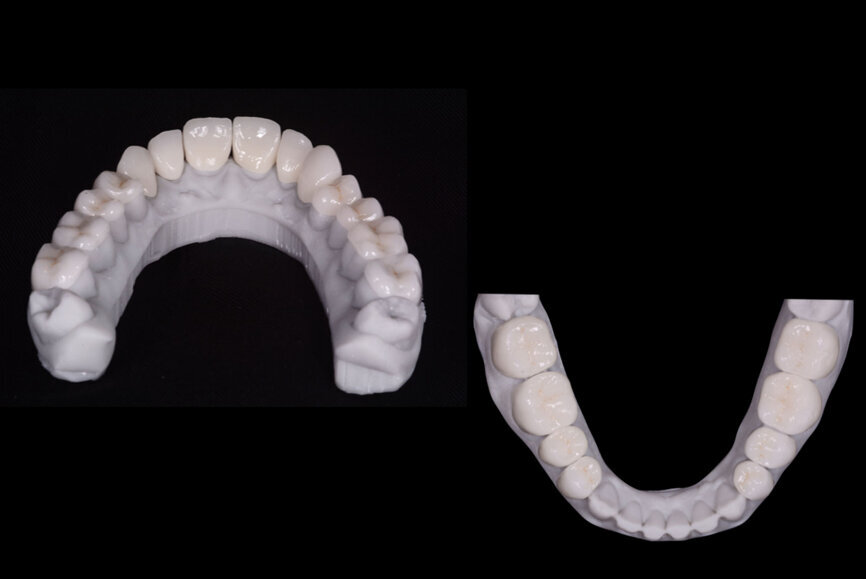

The final veneers and crowns were digitally prepared using the Ceramill Mind design software (Amann Girrbach) and produced in a milling machine (Ceramill Motion 2, Amann Girrbach) from machinable lithium disilicate ceramic blocks (VITABLOCS TriLuxe forte for Ceramill Motion 2, Amann Girrbach; Fig. 10). After confirming the marginal seal and the visual properties through trial insertion, a lip and cheek retractor (OptraGate, Ivoclar Vivadent) was placed in the patient’s mouth.

Fig. 10: Final veneers and crowns digitally prepared using the Ceramill Mind design software and produced in a milling machine (Ceramill

Motion 2) from machinable lithium disilicate ceramic blocks (VITABLOCS TriLuxe forte).